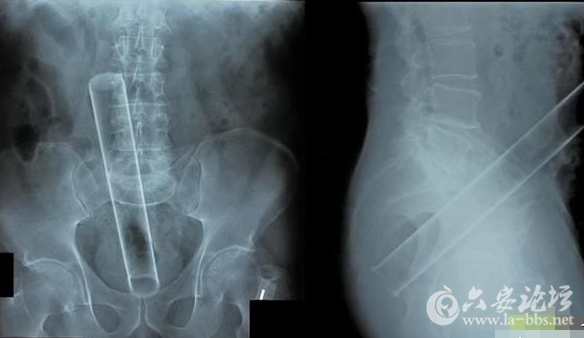

这些让人瞠目结舌的X光片,映射出了女人下体的那点儿事儿,对性有需求是好的,可是要是乱放东西,伤到身体,那可麻烦大了!

这张图片,好像是根钢管?我相信她肯定不是故意的!

告诉我,这不是一根带着尾巴的震动棒!这种深度,难道是进入卵巢了?